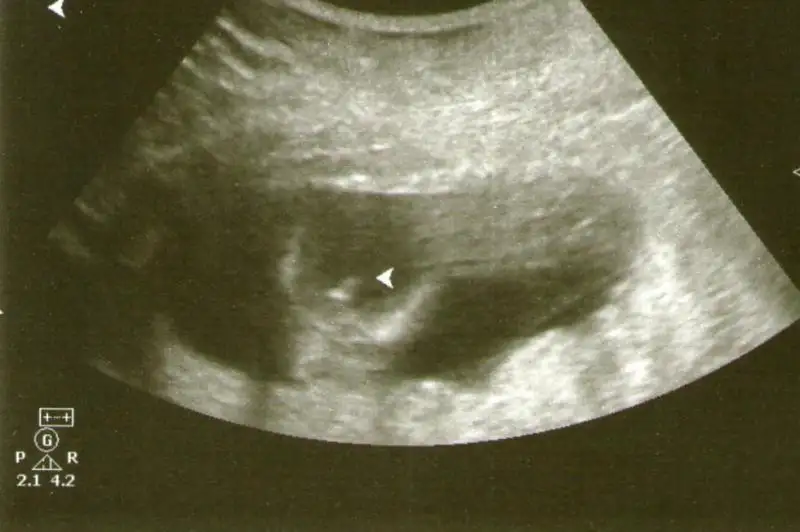

arkadaşlar benim bebeğim 11+2 günlük dokktor cinsiyeti hakkında birşeydemedi sizce nub a göre ne gözüküyor sevgiler

Eklentiler

• $101_5417 (640x480).webp

13,1 KB · Görüntüleme: 111